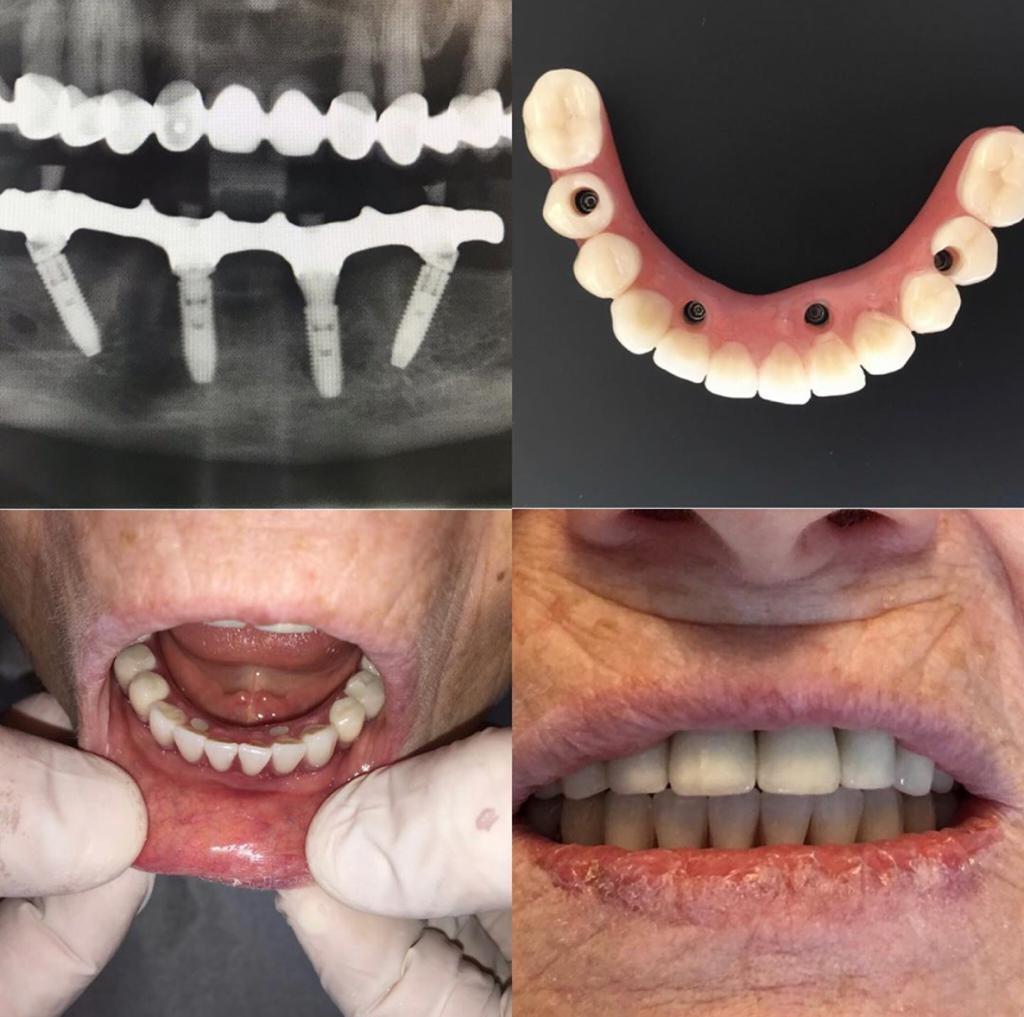

All on Four yöntemi, etkinliği ve hassasiyeti bir arada sunacak şekilde tasarlanmıştır. Genellikle süreç, çenenin üç boyutlu görüntülenmesiyle başlar. Bu aşama, kemik yapısını, sinirlerin konumunu ve implant yerleşimini detaylı olarak analiz etmeyi sağlar. Dijital planlama sayesinde, implant açıları ve protez uyumu önceden simüle edilerek en uygun sonuç elde edilir. Bu süreçte kemik yogunlugu teknolojisi de önemli bir rol oynamaktadır.

Tedavi genellikle şu adımları içerir:

- Hazırlık ve Diş Çekimi: Kalan dişler, kemik yapısı korunarak nazikçe çekilir.

- İmplant Yerleştirme: Dört implant stratejik olarak yerleştirilir; arka implantlar, maksimum destek ve stabilite sağlamak için açılıdır.

- Geçici Protez: Aynı gün geçici dişler takılır, hastalar hemen fonksiyon kazanır.

Bu süreç çoğu zaman tek seansta tamamlanır ve hastalar günü tamamladıklarında işlevsel bir gülümsemeyle klinikten ayrılır.